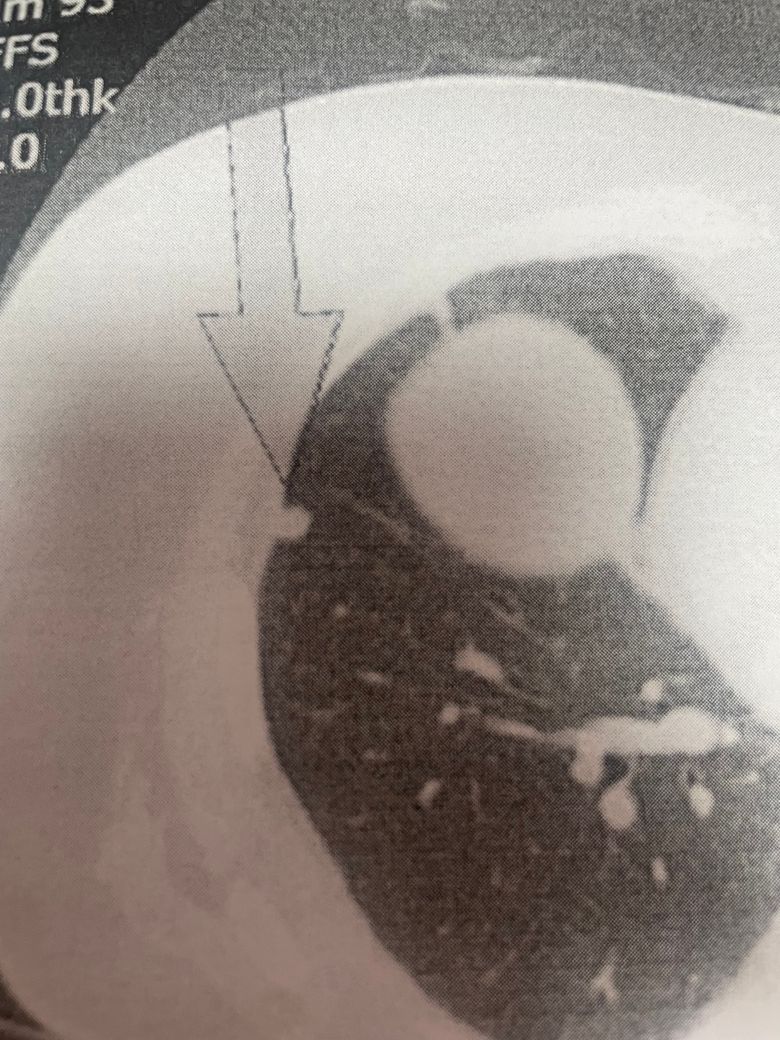

71세이고 여성입니다 22년에는 없었고 23년 3월 코로나 감염되어 2주정도 심하게 아팠고 23년 5월 검진에서 rll 쪽에 8미리 결절이 나왓습니다 그래서 3개월 후인 23.8월에 다시 검사하였고 크기 변화는 없었습니다 24년9월에 검사 하였고 크기가 2미리 커져 10미리가 되어서 3개월후 다시 찍기로 했는데 너무너무 걱정이 되어 질문남깁니다

8mm에서 10mm로 커진 크기는 면밀히 관찰이 필요한 소견입니다만 크기 변화가 느려서 악성 가능성이 낮을 수도 있으므로 지나친 걱정보다 정기적 추적 관찰이 중요합니다. 3개월 뒤 CT를 찍어 추가적 크기 변화나 모양 변화를 확인합니다. 크기, 형태, 경계의 특징, 환자 흡연력, 감염력 등 종합 요소를 통해 판단합니다.

결절 크기가 1cm 이상이고 크기 증가가 관찰되었다면 조직검사나 PET-CT를 고려해볼 수 있으나 이는 검사 결과와 전문의 판단에 따라 결정되며 모든 10mm 이상 결절이 악성은 아닙니다. 현재로서는 크기 변화가 크지 않으므로 다음 검사까지 걱정을 최소화하고 정기 검진에 집중하세요. 필요시 전문의와 상의해 추가적 진단 방법을 결정하여 안심할 수 있도록 하세요.